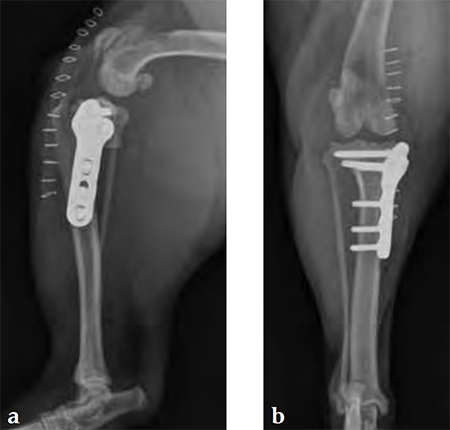

Case 2: Australian cattle dog

(Case provided by Brian Beale, Houston, USA)

An 8-year-old, female, spayed, 24 kg Australian cattle dog. This breed has short stocky legs and is very energetic and strong. The added strength of the 3.5 mm plate over the TPLO 2.7 mm plate was an advantage. The smaller head profile and shorter length of the TPLO 3.5 mm small stature plate allowed it to fit nicely on this patient.